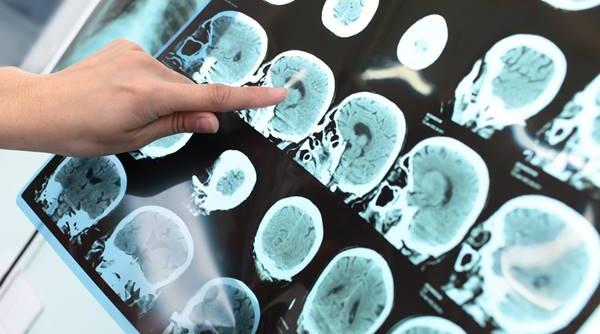

Ministerul Sănătăţii: Program de finanţare a markerilor moleculari pentru stabilirea diagnosticului primar precis în cancerul pulmonar